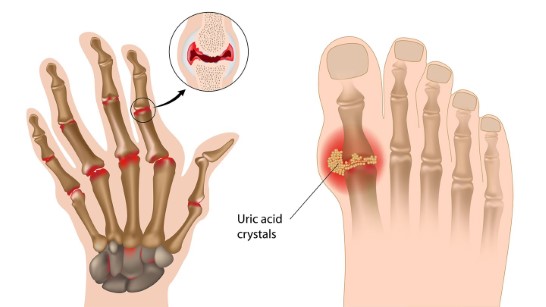

통풍

통풍은 관절염의 한 종류입니다. 관절에서 요산이 빠져나가지못하고 과도하게 축적될때 생깁니다.

바람에도 고통을 느낀다하여 이름이 통풍입니다. 주로 중년남성에게 자주 발병하는 질환입니다.

요산은 원래 소변으로 체내에서 배출되는 노폐물입니다.

이 노폐물이 빠지지않고 쌓이면 작은 결정으로 변할 수 있습니다. 이 결정이 관절에 발생하면 심한 통증을 느끼게 됩니다.

대게 통풍의 첫증상은 엄지발가락에서 시작합니다.

만약 엄지발가락통증이 심하다면 통풍을 의심해볼 수 있습니다.